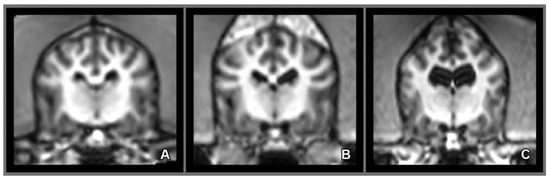

2.5. Morphology and Size of the Measured Brains